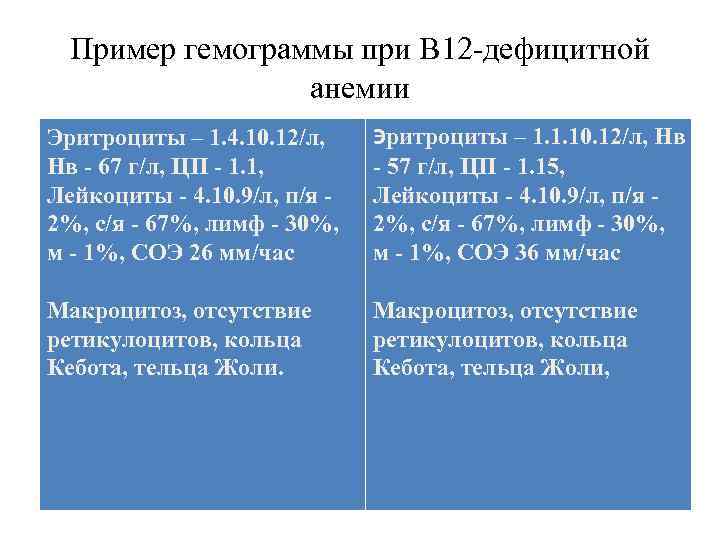

Пример гемограммы при В 12 -дефицитной анемии Эритроциты – 1. 4. 10. 12/л, Нв - 67 г/л, ЦП - 1. 1, Лейкоциты - 4. 10. 9/л, п/я - 2%, с/я - 67%, лимф - 30%, м - 1%, СОЭ 26 мм/час Макроцитоз, отсутствие ретикулоцитов, кольца Кебота, тельца Жоли. Эритроциты – 1. 1. 10. 12/л, Нв - 57 г/л, ЦП - 1. 15, Лейкоциты - 4. 10. 9/л, п/я - 2%, с/я - 67%, лимф - 30%, м - 1%, СОЭ 36 мм/час Макроцитоз, отсутствие ретикулоцитов, кольца Кебота, тельца Жоли,